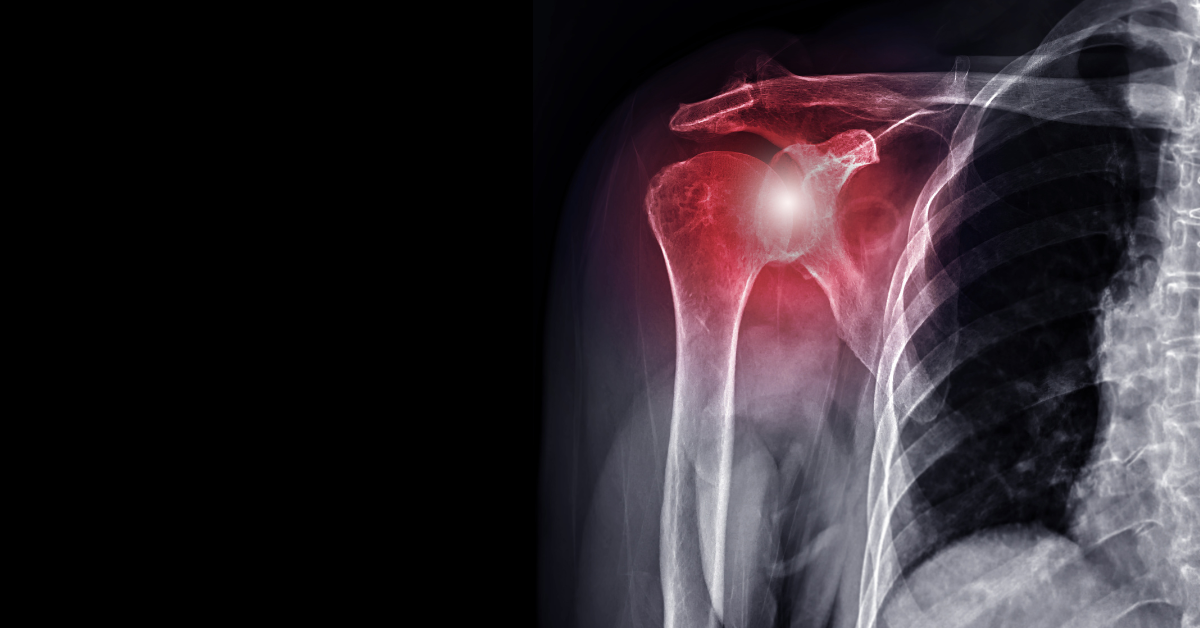

Road to Recovery: ACL Schedule and Timeline

Road to Recovery: ACL Surgery Timeline Discover the step-by-step journey to recovery after ACL surgery with this comprehensive guide. From pre-surgery preparations to post-operative rehabilitation,...